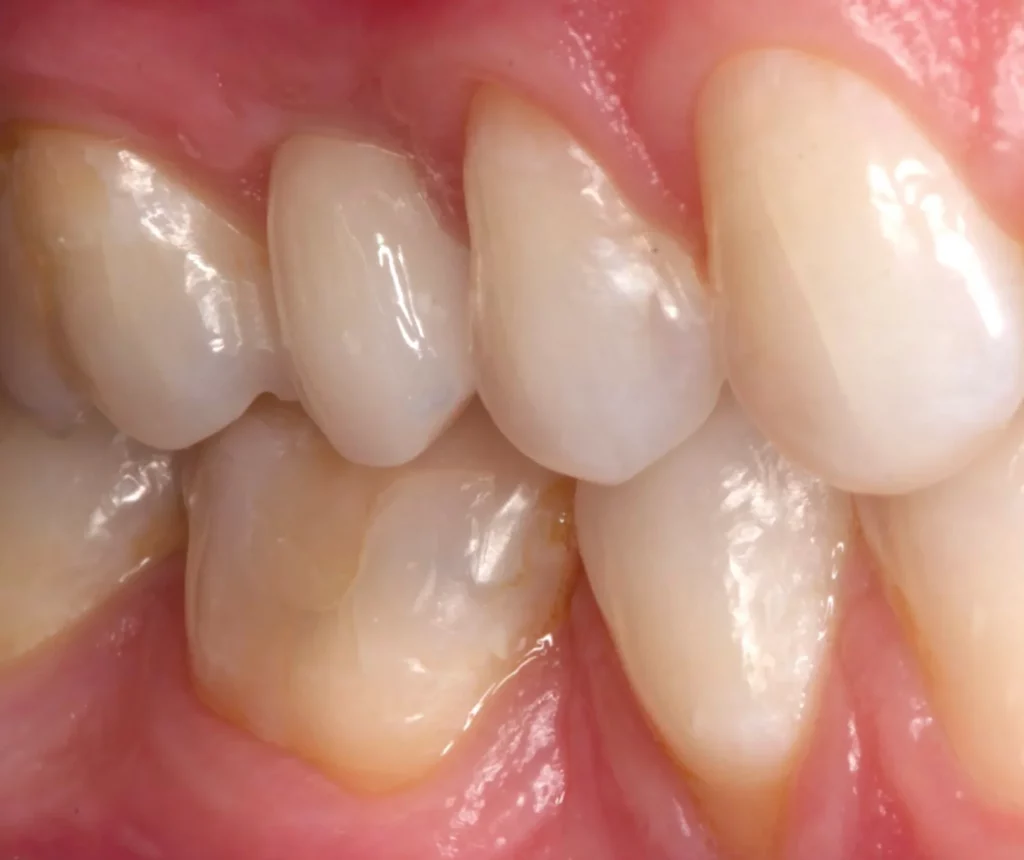

This woman had a badly broken down lower molar that had split apart and had been painfully abscessing for months. Unfortunately, it was beyond saving, and it was extracted. Keen to have the space restored, the patient opted to have an implant placed.

Below shows the crown fitted on to the implant post.